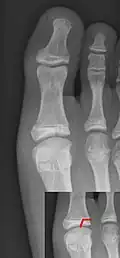

Salter–Harris fracture

A Salter–Harris fracture is a fracture that involves the epiphyseal plate (growth plate) of a bone, specifically the zone of provisional calcification.[2] It is thus a form of child bone fracture. It is a common injury found in children, occurring in 15% of childhood long bone fractures.[3] This type of fracture and its classification system is named for Robert B. Salter and William H. Harris who created and published this classification system in the Journal of Bone and Joint Surgery in 1963.[4]

There are nine types of Salter–Harris fractures; types I to V as described by Robert B. Salter and William H. Harris in 1963,[3] and the rarer types VI to IX which have been added subsequently:[5]

• Type I – transverse fracture through the growth plate (also referred to as the "physis"):[6] 6% incidence

• Type II – A fracture through the growth plate and the metaphysis, sparing the epiphysis:[7] 75% incidence, takes approximately 12-90 weeks or more in the spine to heal.[8]

• Type III – A fracture through growth plate and epiphysis, sparing the metaphysis:[9] 8% incidence

• Type IV – A fracture through all three elements of the bone, the growth plate, metaphysis, and epiphysis:[10] 10% incidence

• Type V – A compression fracture of the growth plate (resulting in a decrease in the perceived space between the epiphysis and metaphysis on x-ray):[11] 1% incidence